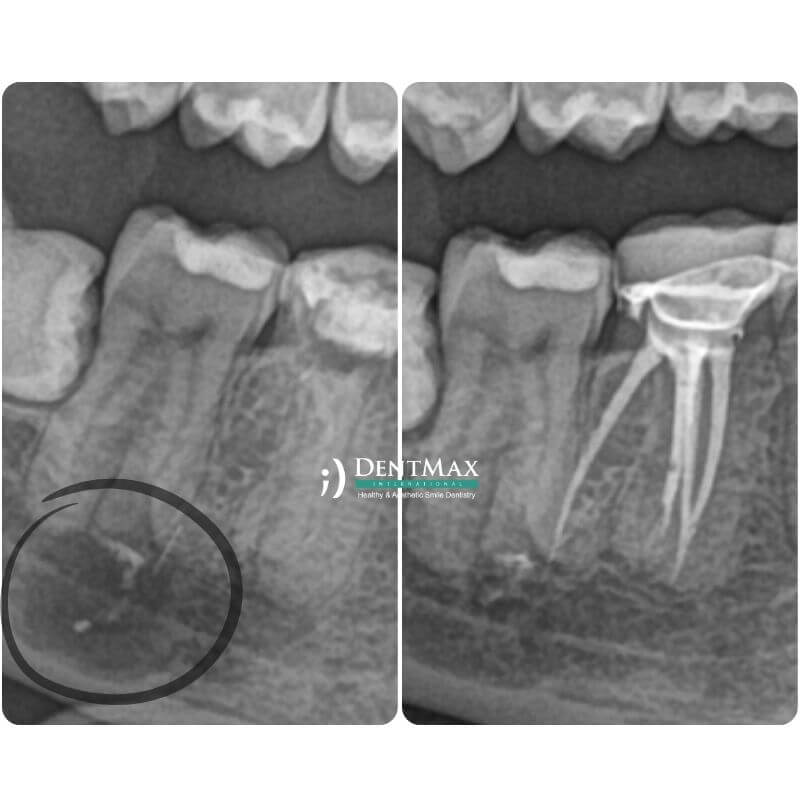

Лечение с MTA

Эндодонтическое лечение с применением МТА